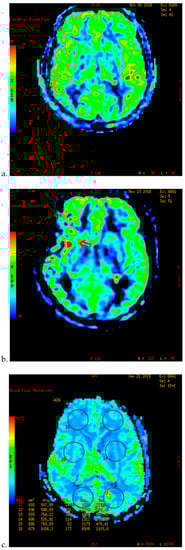

Figure 2.

PWI of patients with TND in the perioperative period after operation (example 2). (a,b) The PWI images of the patients 5 days before operation showed that the cerebral blood flow (CBF) and cerebral blood volume (CBV) of the bilateral hemispheres were basically the same. (c,d) 3 days after the left combined operation, the patients showed blurred vision and dizziness. 6 days after operation, the PWI images showed that the CBF and CBV of the left parietal occipital lobe were significantly higher than those of the opposite side.